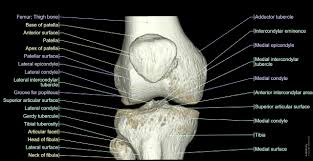

넘어지거나 어디에 부딪힌 후 무릅에 통증을 느낀다면, 무릎과 연결된 허벅지, 정강기, 슬개골 등이 부러졌거나 탈구되었을 가능성이 있습니다.

경골과 대퇴골을 연결하고 경골의 이탈을 방지하는 조직이 찢어졌을 수도 있습니다.

이는 뼈끝의 충돌을 완충시키는 연골이 닮아서 생길 수도 있습니다.